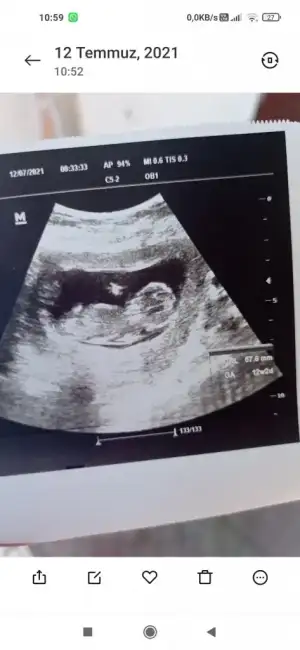

AA evet rengi net olunca çıkıntısı varEki Görüntüle 2895899 Eki Görüntüle 2895900 Az önce instagram üzerinden ücretli bakan birine attım bu şekilde geri dönüş yaptı sizce haklı mı?

Değişme ihtimali var mı peki? Yoksa kesin mi? 11+3 çıktı ama 12+0AA evet rengi net olunca çıkıntısı var![]()

Allah bilir canım erkek görünüyorDeğişme ihtimali var mı peki? Yoksa kesin mi? 11+3 çıktı ama 12+0